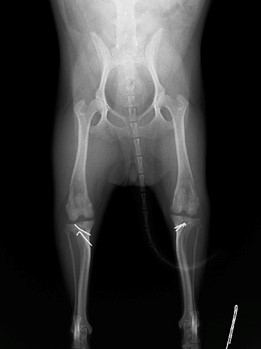

眼球摘出、眼瞼腫瘤切除、チェリーアイ整復、眼瞼縫合、瞬膜フラップ、眼球突出整復、耳介切除、垂直耳道切除、総耳道切除、鼻鏡切除、口腔腫瘍切除(上顎骨切除、下顎骨切除を含む)、各種抜歯(猫の全臼歯抜歯含む)舌腫瘍切除、唾液腺嚢胞切除、皮膚腫瘤切除、断脚(前肢、後肢、片側骨盤切除)、断尾、肺葉切除、胸腺腫切除、心膜切除、横隔膜ヘルニア整復、肝臓腫瘍切除、胆嚢摘出、胃切開、胃拡張胃捻転症候群整復、胃腫瘍切除、腸管切開、腸管腫瘍切除、直腸腫瘍切除(粘膜、全層プルスルーなど)、腎臓摘出、SUB設置手術、脾臓摘出、副腎摘出、膀胱切開、膀胱腫瘍切除(部分切除、全摘出、膀胱尿道一括切除など)、卵巣腫瘍切除、精巣腫瘍切除、卵巣子宮全摘出、肛門嚢切除、各種骨折、膝蓋骨脱臼整復、股関節脱臼整復、大腿骨頭切除、椎間板ヘルニア(各種椎弓切除術)、各種リンパ節切除 など